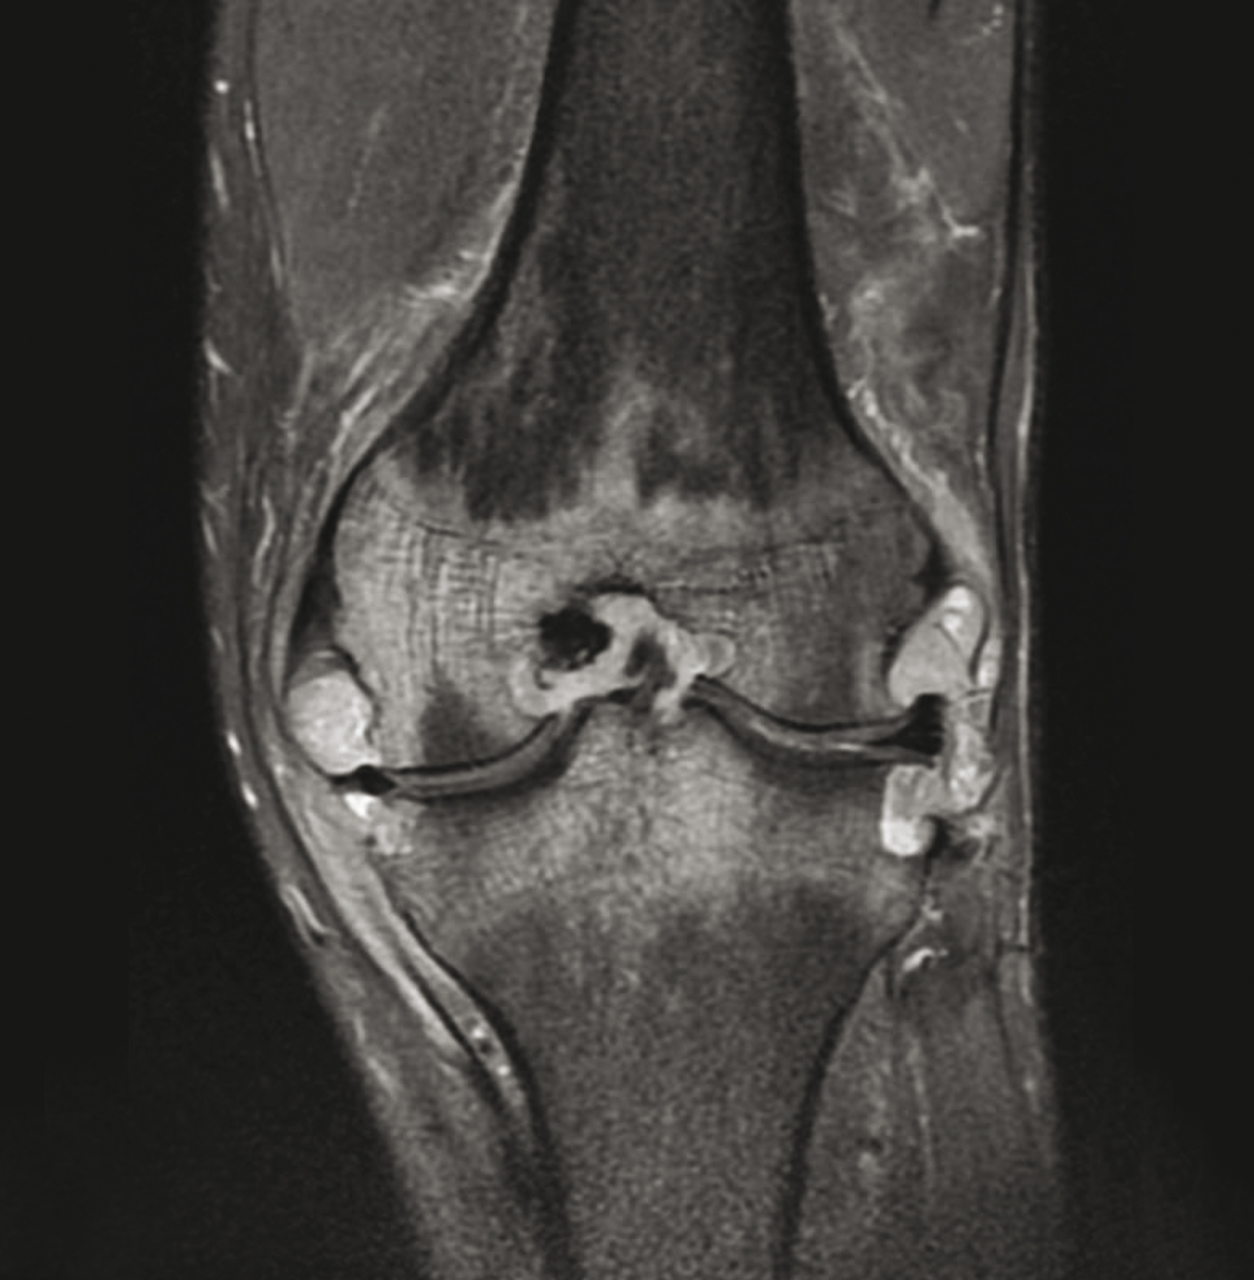

La bonne réponse est : Tuberculose du genou.